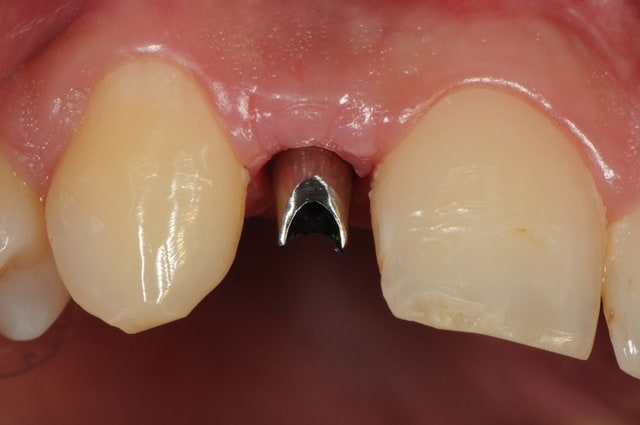

je reviens sur ce cas que j'ai un peu délaissé...

-cicatrisation

-mise en place vis de cica petit diamètre

-ensuite on augmente le diamètre en conservant et en gonflant les tissus gingivaux

-cicatrisation de la première vis de cica,

-diamètre plus gros pour la vis de cica

- pilier pour la provisoire

- provisoire moule ION

- ajustage

- polissage soigneux